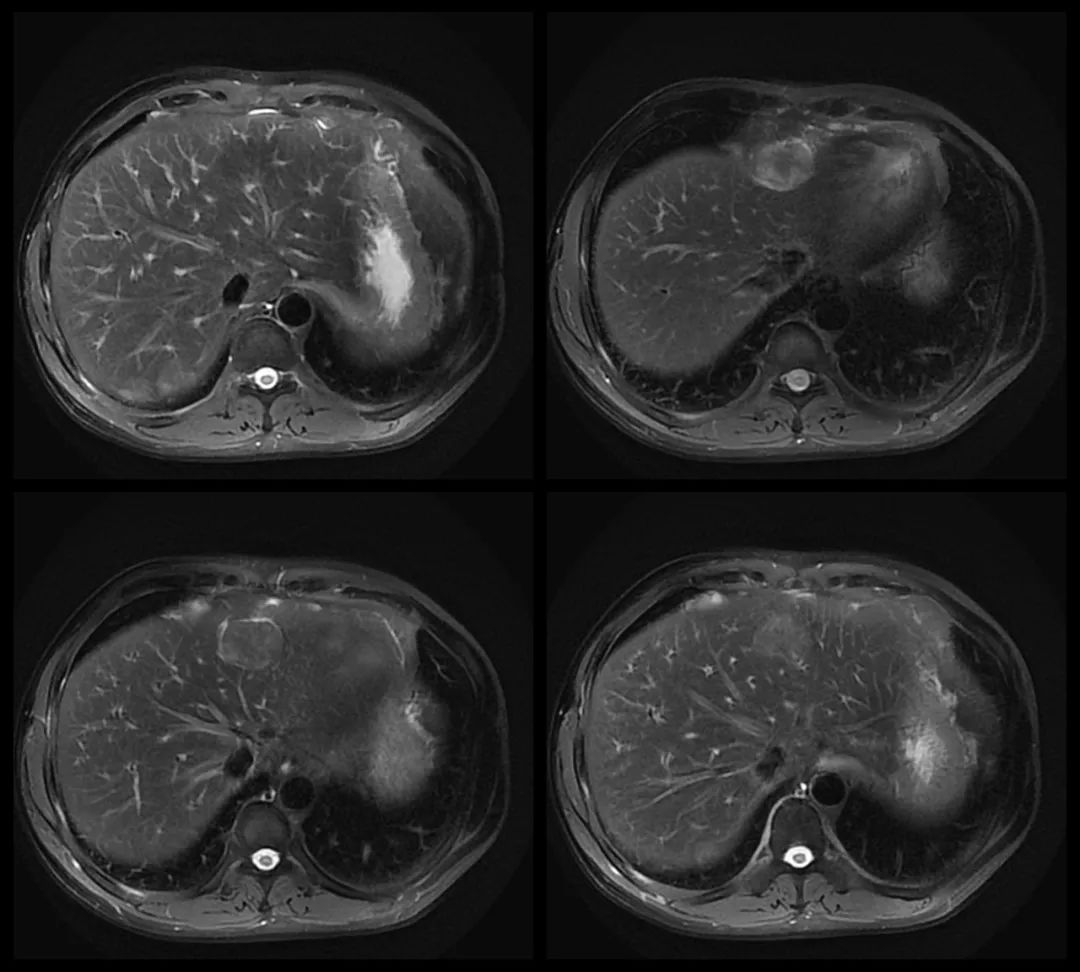

MRI:

MR:多数表现为 T1WI 稍低信号,T2WI 中高信号,与正常脾组织信号相似。增强扫描动脉期、门静脉期和延迟期均为高信号。